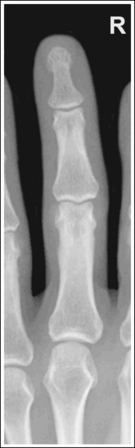

See Figure 4-10 and Box 4-4.

The digit of interest is in a lateral projection. The anterior aspect of the middle and proximal phalanges demonstrates midshaft concavity, and the posterior aspects of the phalanges show slight convexity.

• A lateral finger projection is accomplished by rotating the affected finger 90 degrees from the PA projection (Figure 4-11). Whether the hand is rotated internally or externally to obtain this goal depends on which direction will bring the finger closer to the IR. Typically, when the second and third fingers are imaged, the hand is rotated internally and, when the fourth and fifth fingers are imaged, the hand is rotated externally.

• Distinguishing lateral projection from rotated projection. To understand the difference between a truly lateral digit projection and a lateral projection that is rotated, study a finger skeleton in lateral and PA and AP oblique projections. Note how the midshaft concavity of the middle and proximal phalanges varies as the digit is rotated. In a lateral projection, the anterior aspect of these phalanges is concave, but the posterior aspect demonstrates slight convexity. In PA and AP oblique projections, both sides of the middle and proximal phalangeal midshafts demonstrate concavity, but the side toward which the anterior surface is rotated demonstrates a greater degree of concavity than the side toward which the posterior surface is rotated. The soft tissue width at either side of the phalanx also changes in the lateral and PA and AP oblique projections. More soft tissue is present on the side of the phalanges toward which the anterior surface is rotated (see Image 7).

Image 7

No soft tissue overlap from adjacent digits is present.

• Flex the unaffected fingers into a tight fist, allowing the finger of interest to remain extended. To visualize the proximal phalanx, it may be necessary to extend the affected finger with an immobilization device or to tape the unaffected fingers away from the affected finger. If the unaffected fingers are not drawn away from the proximal phalanx of the affected finger, they will be superimposed on the area, preventing adequate visualization (see Image 8). An immobilization device should not be used to extend the finger if a fracture is suspected and the device causes stress to the fractured area (see Image 9).

The IP joints are visible as open spaces, and the phalanges are not foreshortened.

• The IP joints are open, and the phalanges are demonstrated without foreshortening as long as the finger was positioned parallel with the IR and the central ray was perpendicular to and centered with the PIP joint.

• When the third and fourth digits are imaged, they are positioned at a greater OID than the second and fifth digits. To keep the third and fourth digits parallel with the IR, it may be necessary to place an immobilization device beneath their distal phalanges. When a finger is not positioned parallel with the IR and perpendicular to the central ray, the IP joint spaces are closed and the phalanges are foreshortened.

The PIP joint is at the center of the exposure field. The distal, middle, and proximal phalanges and the metacarpal head of the affected digit are included within the collimated field.

• Center a perpendicular central ray to the PIP joint to place it in the center of the image. Open the longitudinal collimation to include the distal phalanx and the metacarpal head. Transversely collimate to within 0.5 inch (1.25 cm) of the finger skin line.

Concavity is demonstrated on both sides of the middle and proximal phalangeal midshafts, indicating that the finger was not adequately rotated for this image.

The unaffected fingers were not flexed enough to prevent soft tissue or bony superimposition of the affected digit's proximal phalanx.

Tightly flex the unaffected fingers away from the affected finger. Hyperextending the affected finger with an immobilization prop may also help increase demonstration of the proximal phalanx if a fracture of this area is not suspected.